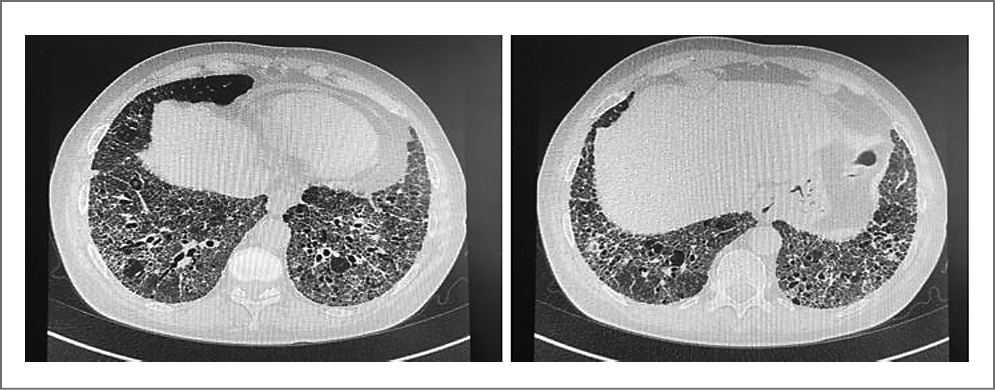

Пациентка П. 1956 года рождения (60 лет) обратилась в областной консультативно-диагностический центр для больных пульмонологического профиля Областной клинической больницы №3 г. Челябинска в декабре 2016 г. с жалобами на одышку смешанного характера при умеренной физической нагрузке, сухой приступообразный кашель по утрам. Из анамнеза известно, что одышка беспокоит последние 2 года при подъеме по лестнице на четвертый этаж, за 6 мес до обращения к пульмонологу одышка стала прогрессировать. В поликлинике по месту жительства при выполнении обзорной рентгенографии органов грудной клетки выявлены очаговые тени небольших размеров, преимущественно в базальных отделах, рекомендована ВРКТ. В январе 2017 г. впервые проведена ВРКТ органов грудной клетки: в нижних отделах обоих легких, преимущественно в базальных и субплевральных отделах, значительно выражены ретикулярные изменения, тракционные бронхо- и бронхиолоэктазы, участки формирования «сотового легкого»; симптом «матового стекла» в зонах ретикулярной исчерченности (рис. 1).

Рис. 1 Компьютерные томограммы органов грудной клетки пациентки П., 2017 г.